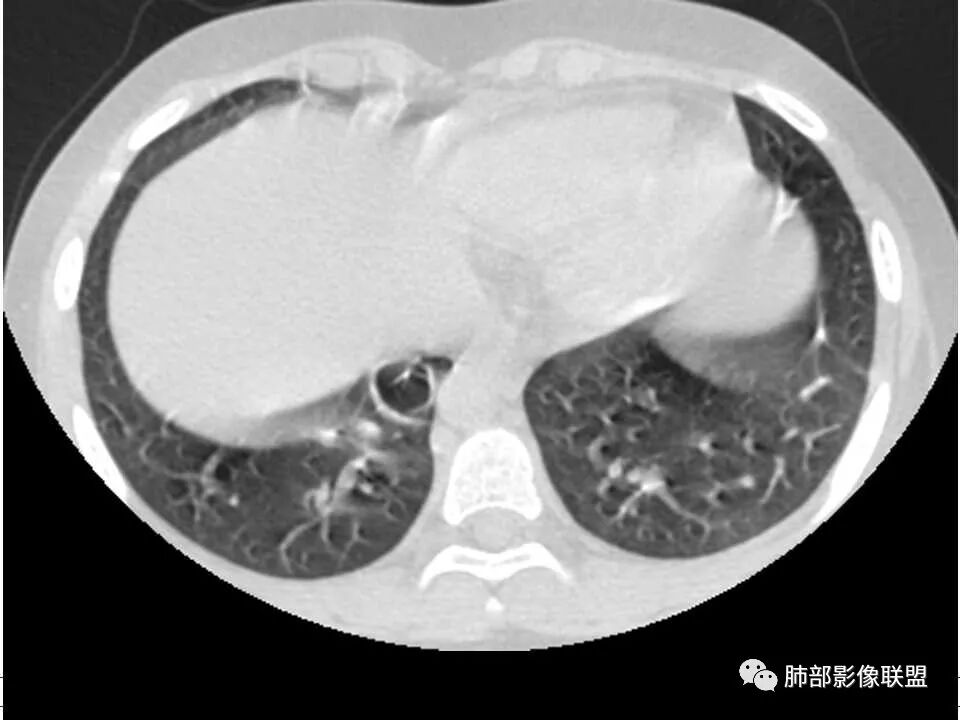

2.双肺多发片影,随机分布,多空洞或囊腔,胸膜下多楔形影,气道未见受累等等符合脓毒血症影像学表现,尤其是金葡。

双肺多发空洞、结节及胸膜下楔形密度增高影,结合临床考虑:1.金葡菌肺感染。2脓毒性肺栓塞。

儿童,发热,急性起病,右下肢骨水肿,两肺弥漫性病变,伴囊,胸膜下分布,部分呈楔形,血道分布,符合金葡菌感染,脓毒肺栓塞

男,8岁,两肺多发随机分布结节空洞影,壁光整,考虑血道来源,结合右侧膝关节有骨髓水肿信号,临床感染指标明显增高,考虑骨髓炎并血道播散,金葡菌感染?LCH小孩骨头症状相对较轻,放在代排吧。